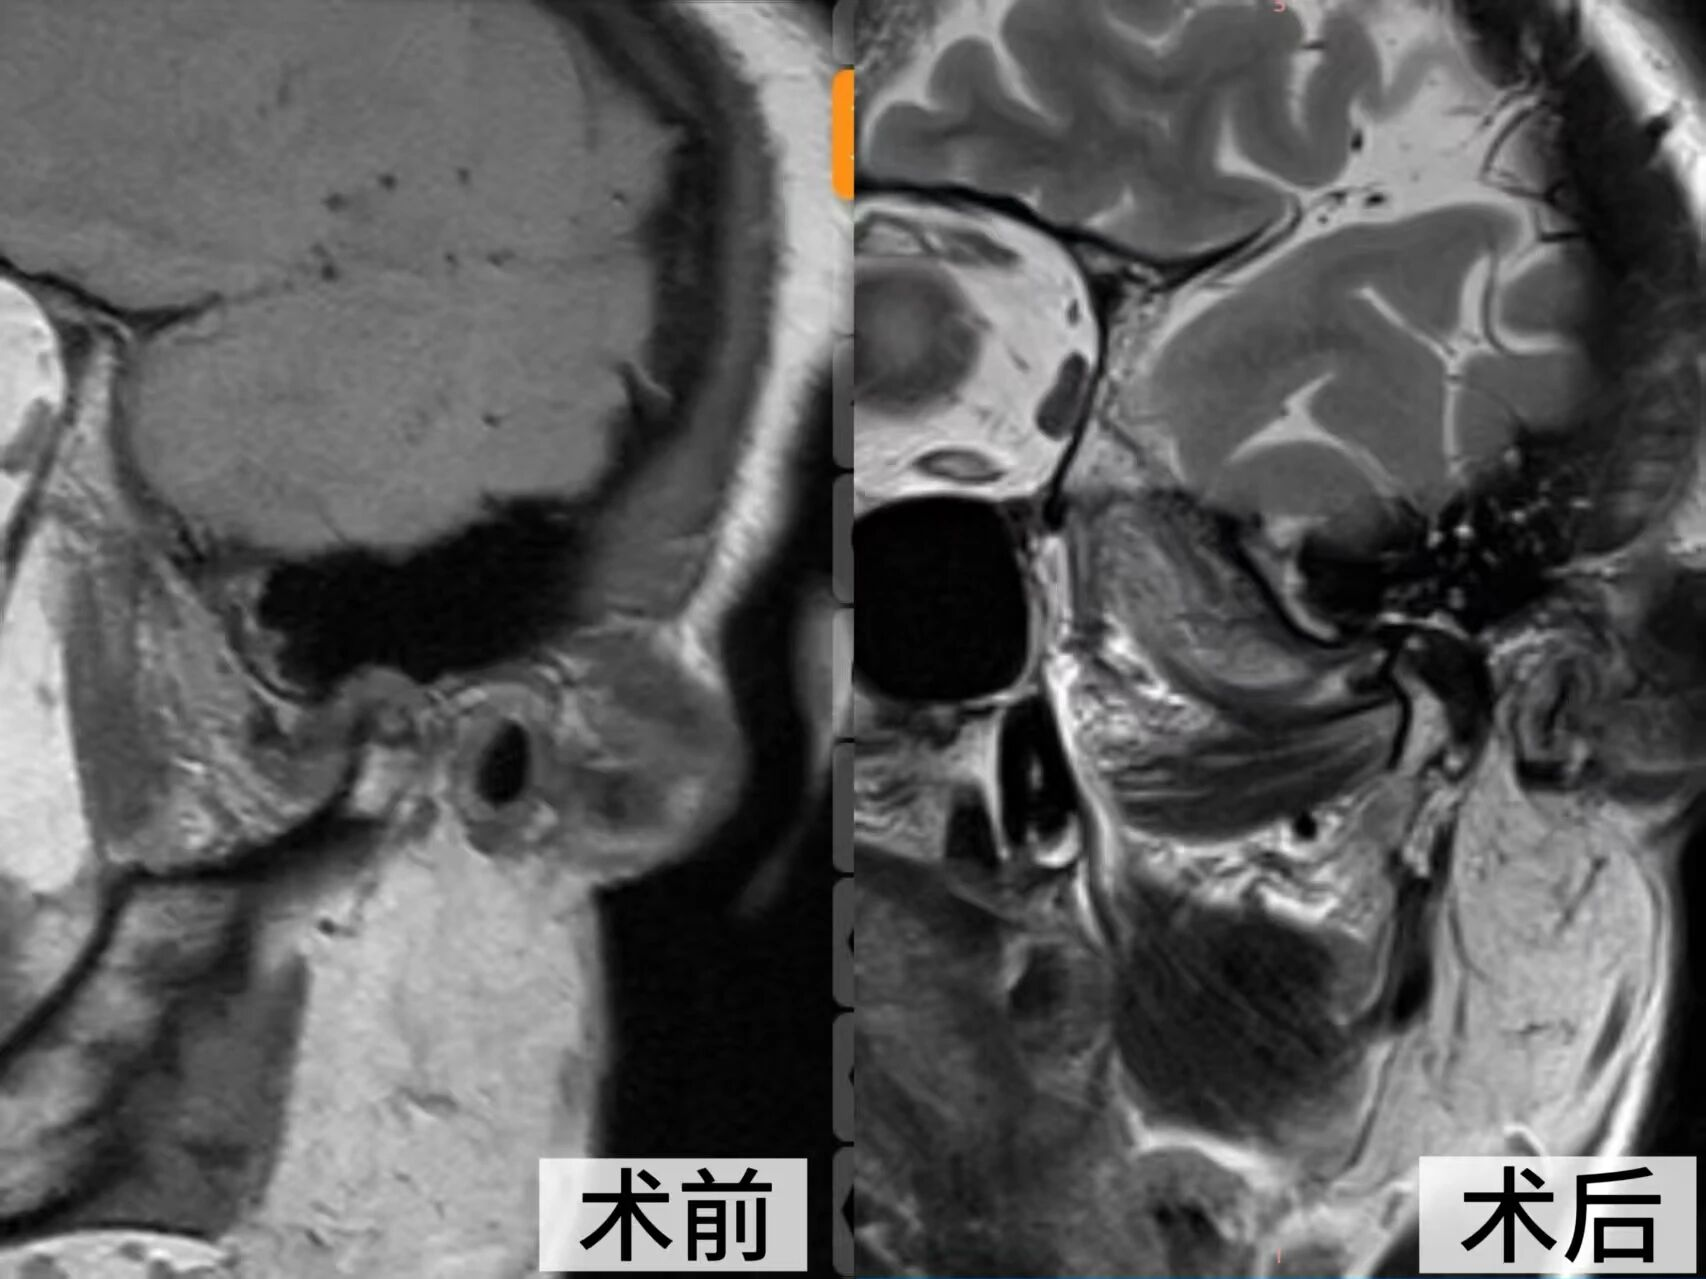

经详细检查,她的症状被确诊为 “左侧颞下颌关节不可复性盘前移位”,关节盘已严重变形、粘连伴髁突骨折破坏,必须通过外科手术才能从根本上解决问题。

面对这一复杂病例,口腔颌面整形创伤外科主任王学玖组织团队开展多次术前讨论。鉴于患者关节结构破坏严重,常规的关节镜微创手术已难以奏效,团队最终决定为其施行开放性颞下颌关节手术。

王学玖团队在患者耳前设计了精巧的隐蔽切口,娴熟地避开重要神经血管,充分暴露病变的颞下颌关节,清晰地见到关节盘已完全脱位并粘连于前内侧,盘后区组织糜烂。团队精准地完成了关节盘的松解、复位与固定,重建了正常的关节结构。

术后,司女士恢复良好,困扰多年的关节区疼痛显著缓解,张口度也较之前明显改善。目前,在医护人员的精心治疗和护理下,她已开始准备进行系统的张口训练,并对未来的生活质量充满了信心。“今后终于能踏实地吃一顿饭了!”